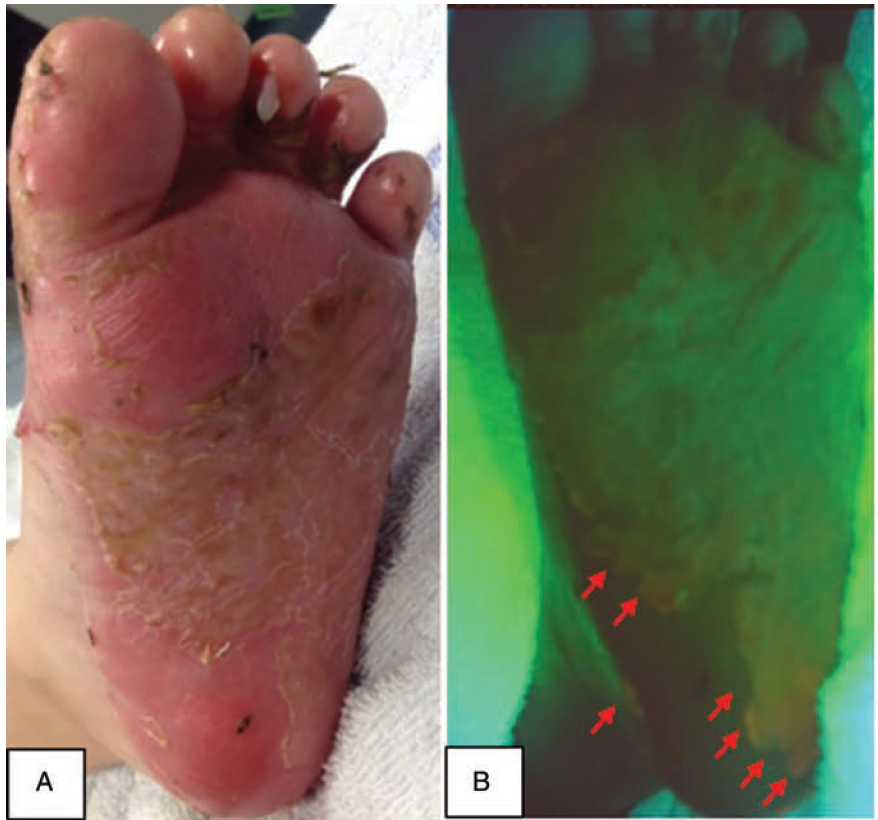

Point-of-care fluorescence imaging reveals extent of bacterial load in diabetic foot ulcers

Armstrong, DG et al. Int Wound J 2023

The Use of Point-of-Care Bacterial Autofluorescence Imaging in the Management of Diabetic Foot Ulcers: A Pilot Randomized Controlled Trial

Rahma, S. et al. Diabetes Care 2022